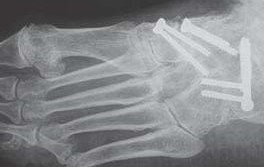

Unter den Mittelfußbereich fällt die Lisfranc- (blau), die Bona-Jäger- (grün) und Chopart- (rot) Gelenkreihe

Die Lisfranc-Gelenkreihe wird aus den Ossa cuneiformia/Os cuboideum und den jeweiligen Metatarsalia gebildet. Die Bona-Jäger-Gelenkreihe liegt zwischen dem Os naviculare und den Ossa cuneiformia. Die Chopart-Gelenkreihe wird aus Talus/Calcaneus und Os naviculare/Os cuboideum gebildet. Vor allem ist die Lisfranc-Gelenk-Linie von degenerativen Veränderungen betroffen, hierbei häufiger die mediale Säule, also die Tarsometatarsal-Gelenke I-III.